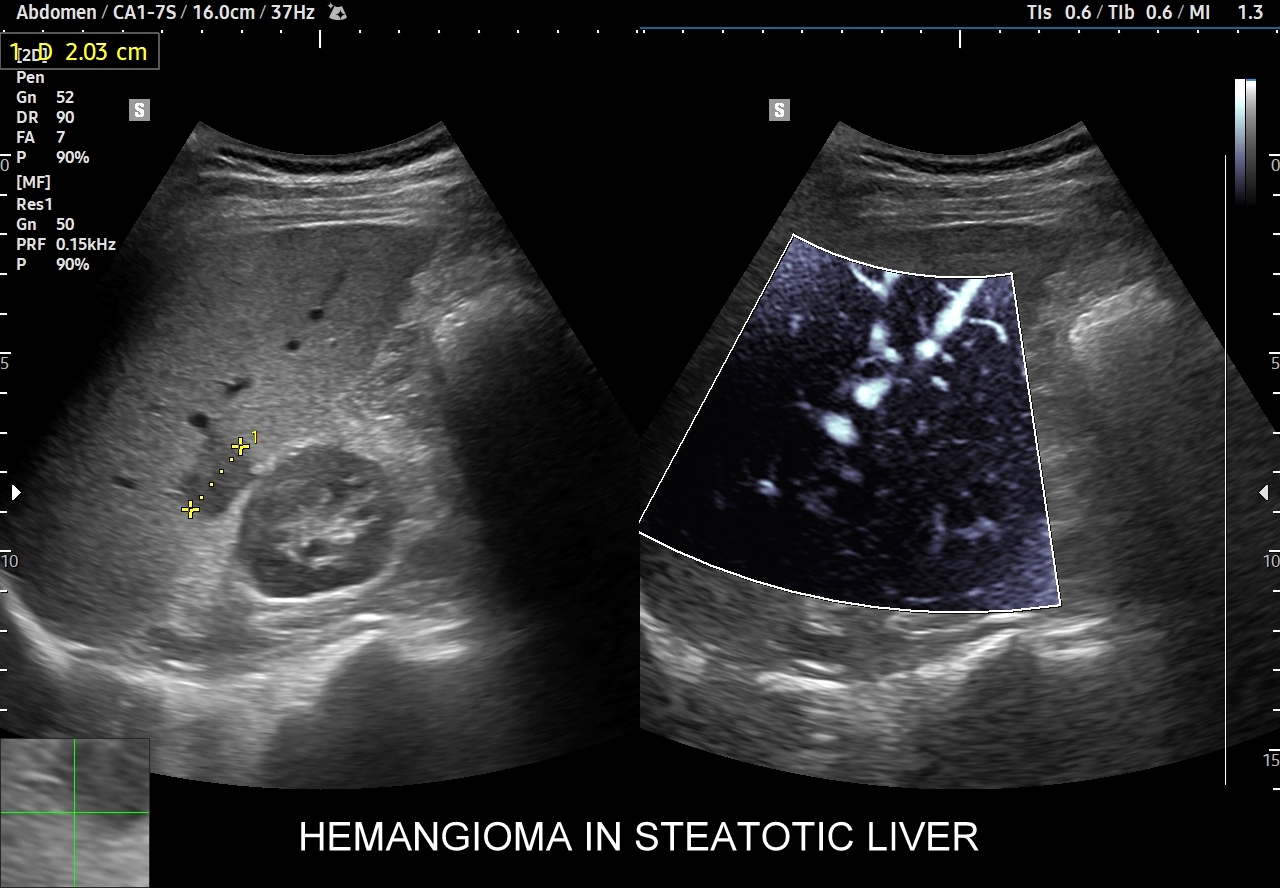

Naczyniaki duże, tj. powyżej 2-3 cm, mogą mieć strukturę niejednorodną echogenicznie, w tym obszary hypoechogenne. Spotyka się także naczyniaki o charakterystyce normo- lub hypechogenicznej, w szczególności w wątrobie stłuszczonej. Z powyższych względów należy mieć na uwadze i zapamiętać, że badanie USG w podstawowym trybie B nie jest wystarczające do postawienia rozpoznania naczyniaka wątroby. W ramach obrazowej diagnostyki różnicowej najbardziej pomocnym jest badanie USG z kontrastem (CEUS), w którym to naczyniak wątroby posiada charakterystyczny wzorzec wypełnienia.

W badaniu USG w prezentacji B w niestłuszczonej wątrobie typowy naczyniak włośniczkowy lokalizuje się w pobliżu gałęzi żyły wątrobowej, a prezentuje się jako ostrookonturowana, hyperechogenna, jednorodna, krągła lub owalna zmiana ogniskowa. Ze względu na niską prędkość przepływu krwi i wynikające z tego ograniczenie detekcji w trybie color-Doppler w naczyniaku nie rejestruje się sygnału. Z kolei w trybie mikrounaczynienia (MVI / MVF) w zależności od czułości aparatury w naczyniaku można zaobserwować delikatny sygnał w postaci „poprószonego śniegu”.